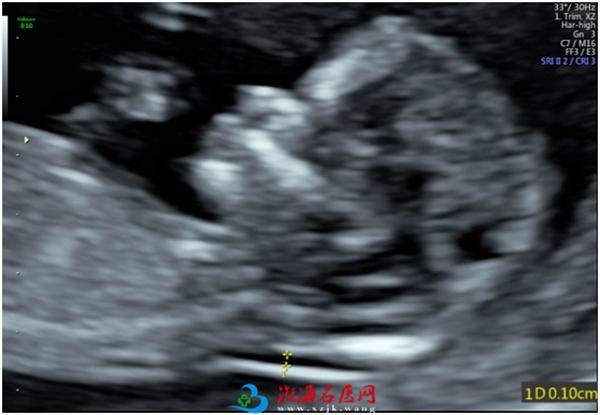

3、胎儿鼻骨(NB)

胎儿鼻骨是筛查染色体异常的指标之一。鼻骨长短及骨化程度与孕龄有关。

4、静脉导管

静脉导管A波倒置或缺失是预测胎儿异常的一个重要指标。